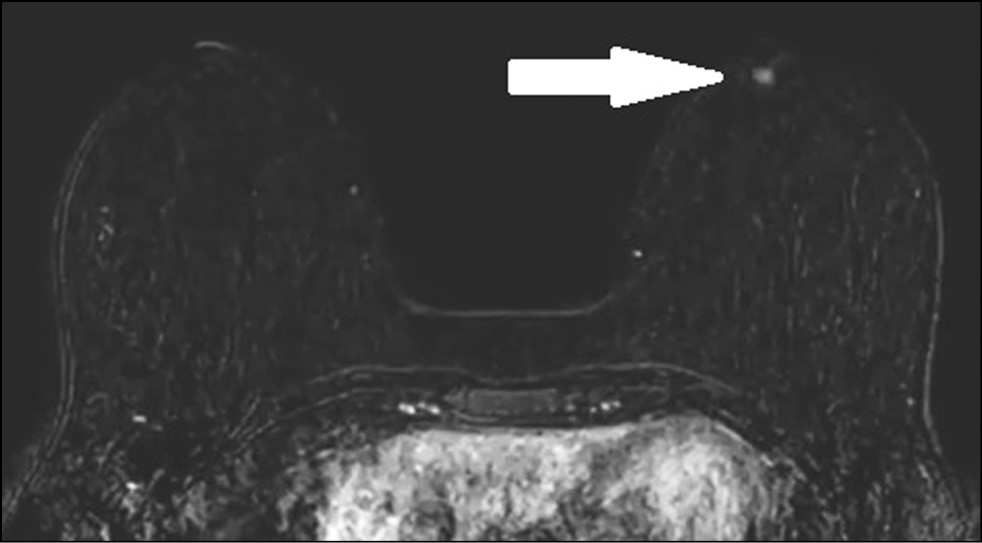

A 38-year-old patient complained of 1-month itching of the right nipple and skin discoloration. Breast ultrasonography and mammography findings (Figs. 5 and 6) were normal. The breast was examined by contrast-enhanced MRI. The early postcontrast series revealed a right nipple mass homogeneously accumulating a contrast agent (Fig. 7). A parametric map showed a nipple mass with rapid contrast enhancement and subsequent elimination, a type III graphic curve (Fig. 8). Morphological verification revealed nipple adenoma.

Figure 7. Magnetic resonance imaging of a nipple adenoma (early postcontrast series): a right nipple mass homogeneously accumulating a contrast agent (arrow).

Figure 8. Magnetic resonance imaging of a nipple adenoma (parametric map): a right nipple mass with rapid contrast enhancement and subsequent elimination, type III graphic curve.